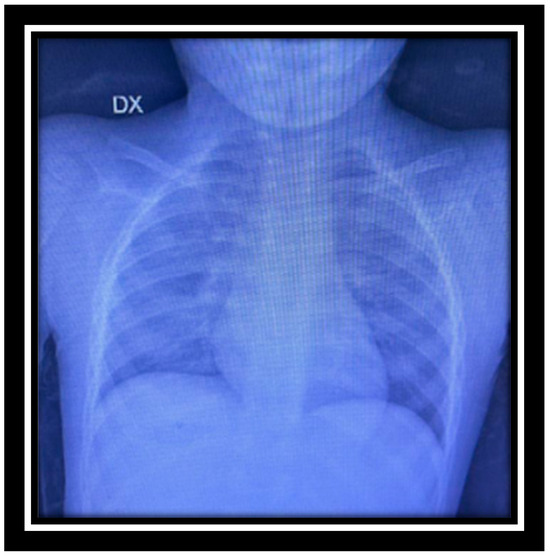

| Chest X-ray | mild accentuation of the bronchial structure |